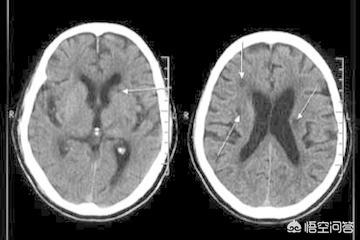

Vingt-quatre à 48 heures après l'apparition de l'infarctus cérébral, la tomodensitométrie du cerveau montre des foyers de faible densité dans les zones correspondantes, avec des limites mal définies, qui peuvent avoir un certain effet d'occupation. L'examen par résonance magnétique cérébrale (IRM) permet de détecter l'infarctus cérébral à un stade plus précoce, ce qui se manifeste par un signal T1 faible dans la zone de la lésion et un signal T2 élevé sur l'image pondérée, et l'IRM permet de détecter des foyers d'infarctus plus petits.

Les lésions d'infarctus cérébral caverneux sont petites et ne sont facilement reconnaissables que par les spécialistes, avec des lésions multiples au milieu de la section cérébrale de l'IRM.